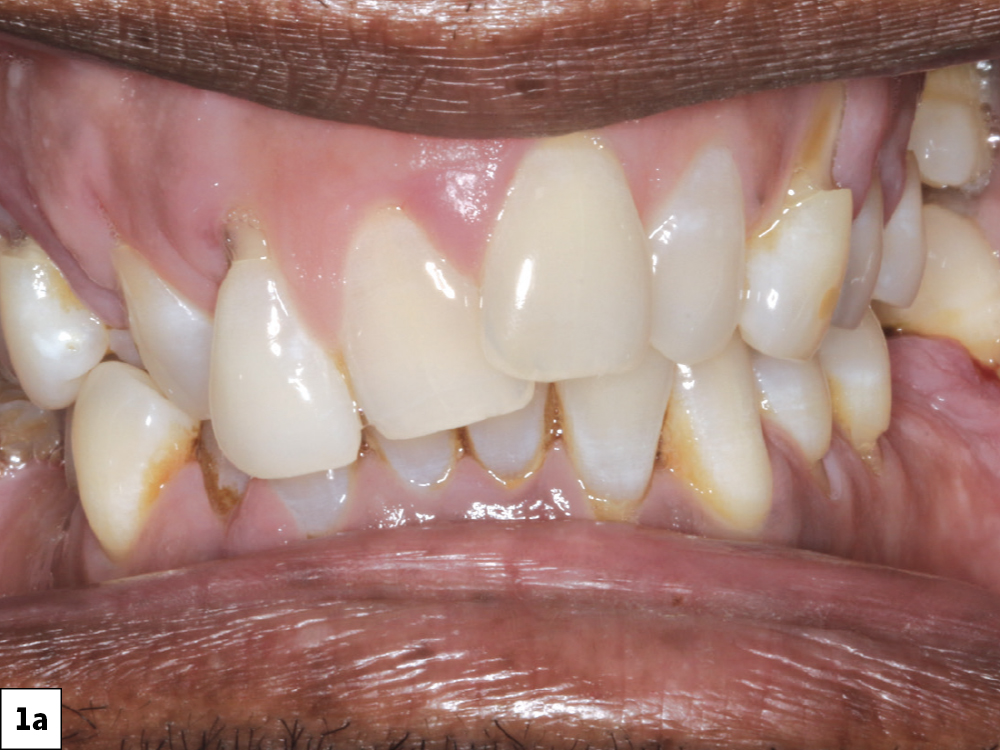

Figures 1a, 1b: The desire for improved esthetics motivated the patient to seek consultation. A retracted view shows the patient’s anterior misalignment and malocclusion in the maxillary arch. CBCT analysis showed extensive periodontal bone loss that warranted extraction and implant reconstruction in the maxilla and posterior mandible.